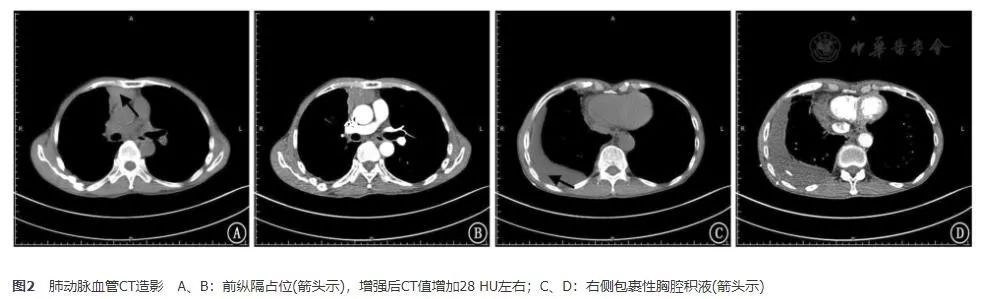

入院后查甲状腺及颈部淋巴结B超未见异常。肺通气灌注显像提示:右肺下叶前基底段、后基底段及左肺上叶尖后段多发通气与血流灌注下降灶(匹配);余双肺通气及血流灌注未见异常,无肺栓塞依据。经过胸腔抽液后,复查肺动脉血管CT造影(2017年11月24日)提示肺血管未见明显异常,前纵隔占位(增强后CT值增加28 HU左右);两肺下叶炎症、右侧胸腔积液,较前片(2017年11月15日)好转;两肺多发纤维灶,右肺上叶微小结节(图2)。

图2 肺动脉血管CT造影 A、B:前纵隔占位(箭头示),增强后CT值增加28 HU左右;C、D:右侧包裹性胸腔积液(箭头示)